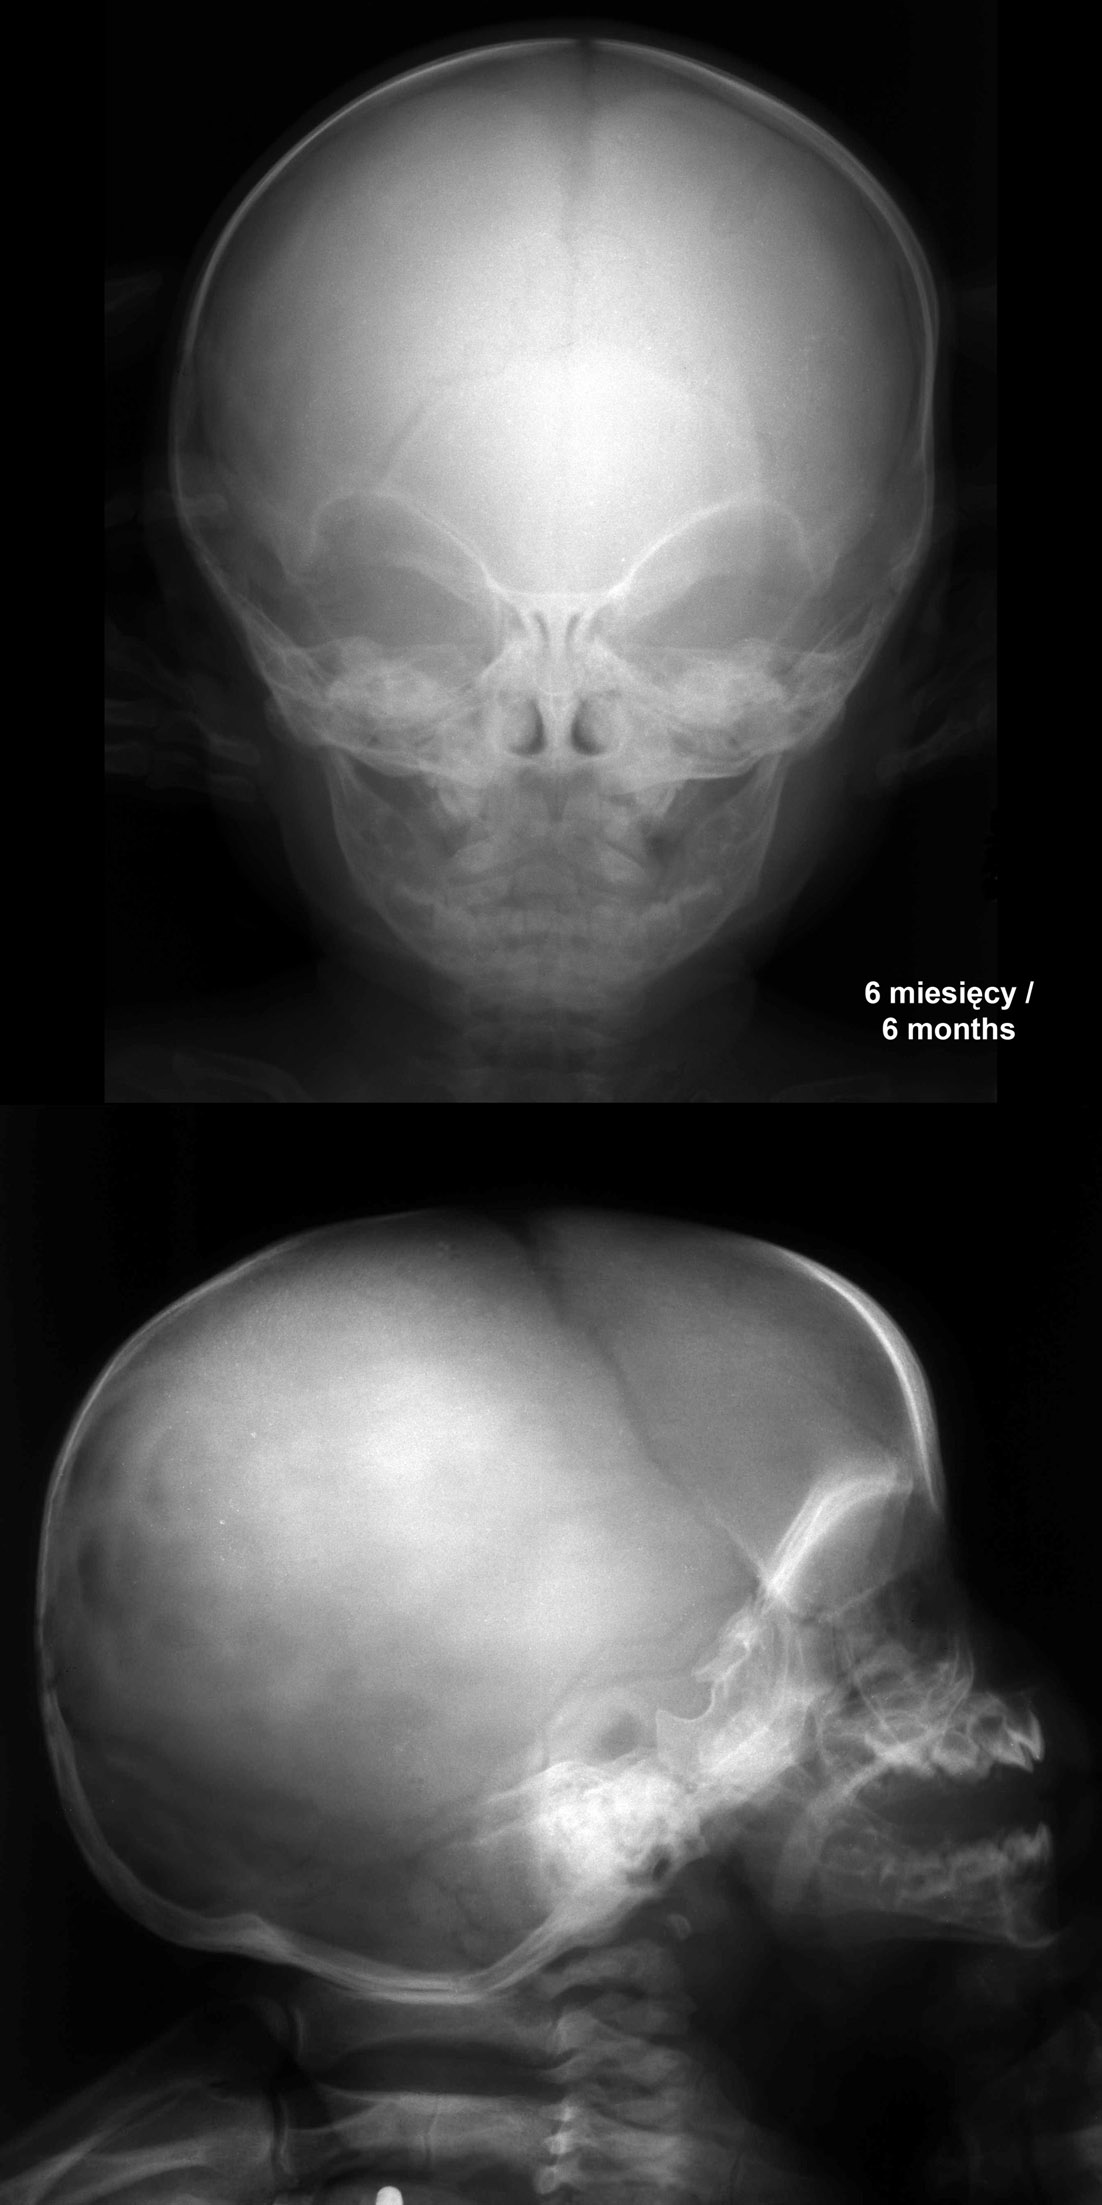

RTG głowy 6-miesięcznego dziecka.

RTG głowy rocznego dziecka.